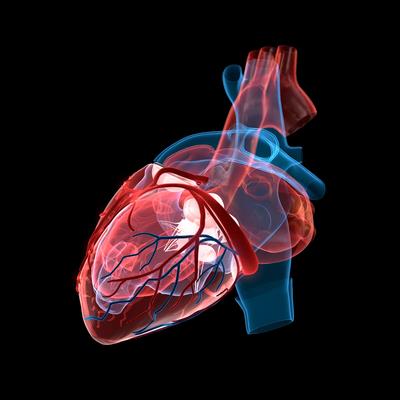

61QhzyaN0mL._AC_UF1000,, Methods in Treating Heart Failure - Device and Surgery,

Methods in Treating Heart Failure - Device and Surgery, Acute Heart Failure: Putting the Puzzle of Pathophysiology,

Acute Heart Failure: Putting the Puzzle of Pathophysiology, Back to Basics: Heart failure medication - Issues and Answers,

Back to Basics: Heart failure medication - Issues and Answers, CONGESTIVE HEART FAILURE: THE ULTIMATE GUIDE TO,